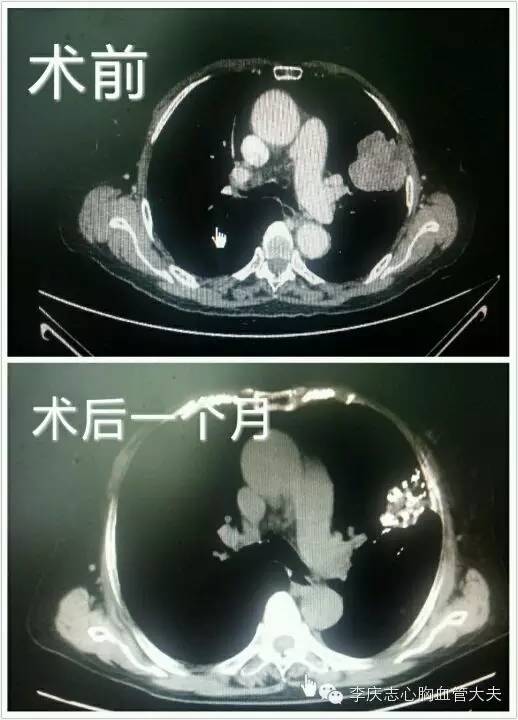

典型病例2 陈老太,67岁,经穿刺诊断为肺鳞癌,患者本人强烈拒绝手术,属于“不愿意手术”的病人,行肺癌粒子植入后肿物明显缩小。